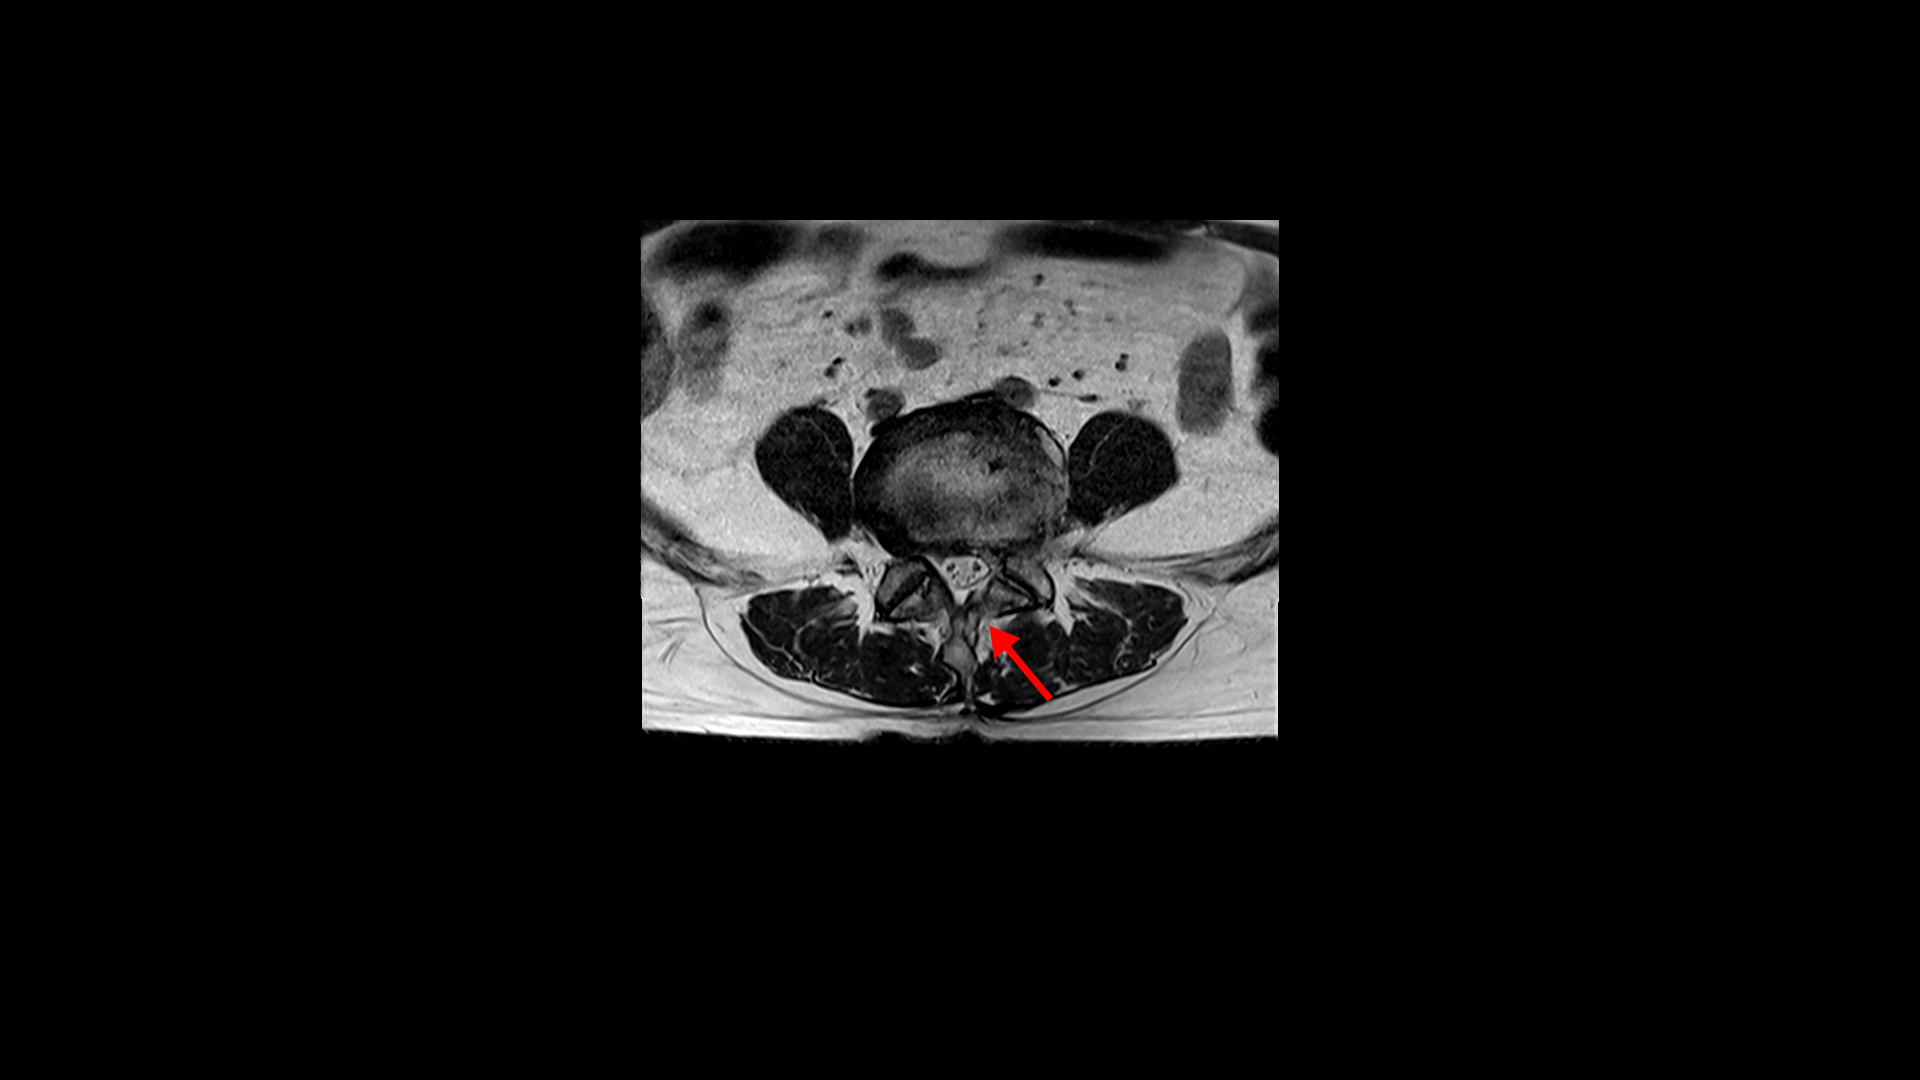

4번 5번은 왼쪽 신경이 빠져나가는 추간공이 뼈가 자라면서 좁아져 추간공협착이 있습니다.

또 왼쪽 후궁에는 과거에 받은 수술의 흔적도 보입니다.